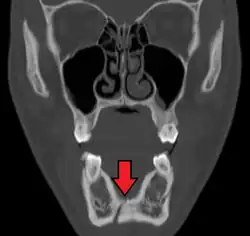

Plain film radiography

Traditionally, plain films of the mandible would be exposed but had lower sensitivity and specificity owing to overlap of structures. Views included AP (for parasymphsis), lateral oblique (body, ramus, angle, coronoid process) and Towne's (condyle) views. Condylar fractures can be especially difficult to identify, depending on the direction of condylar displacement or dislocation so multiple views of it are usually examined with two views at perpendicular angles.[11]

Panoramic radiography

Panoramic radiographs are tomograms where the mandible is in the focal trough and show a flat image of the mandible. Because the curve of the mandible appears in a 2-dimensional image, fractures are easier to spot leading to an accuracy similar to CT except in the condyle region. In addition, broken, missing or malaligned teeth can often be appreciated on a panoramic image which is frequently lost in plain films. Medial/lateral displacement of the fracture segments and especially the condyle are difficult to gauge so the view is sometimes augmented with plain film radiography or computed tomography for more complex mandible fractures.

Computed tomography

Computed tomography is the most sensitive and specific of the imaging techniques. The facial bones can be visualized as slices through the skeletal in either the axial, coronal or sagittal planes. Images can be reconstructed into a 3-dimensional view, to give a better sense of the displacement of various fragments. 3D reconstruction, however, can mask smaller fractures owing to volume averaging, scatter artifact and surrounding structures simply blocking the view of underlying areas.

Research has shown that panoramic radiography is similar to computed tomography in its diagnostic accuracy for mandible fractures and both are more accurate than plain film radiograph.[12] The indications to use CT for mandible fracture vary by region, but it does not seem to add to diagnosis or treatment planning except for comminuted or avulsive type fractures,[13] although, there is better clinician agreement on the location and absence of fractures with CT compared to panoramic radiography.[14]